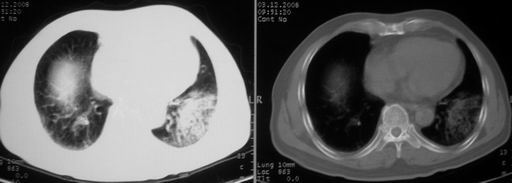

ct左肺下叶大片状高密度影,病变密度不均,界限不清,左侧胸腔积液,治疗后复查临床症状好转而影像学表现病变有发展,还是首先考虑感染性病变,复查时间短附合感染性病变的病理改变。

两肺炎症感染(以左肺下叶为著),双侧少量胸腔积液;建议继续抗炎治疗。